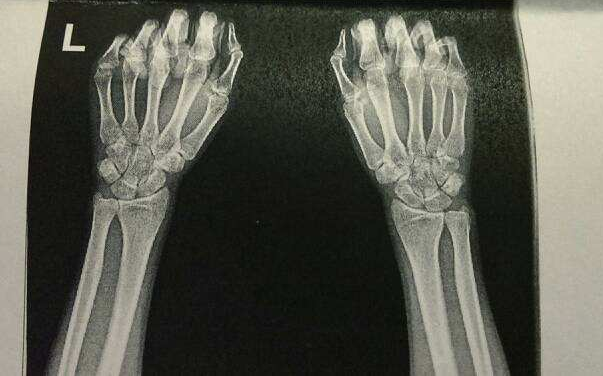

2.临床化学家

临床化学是临床病理学的领域之一,主要注重体液的分析。使用简单化学方法检测血液和尿液的学科是在19世纪晚期发展起来的。在此之后,包括酶活性、分光光度法、电泳与免疫测定等检测技术相继得到应用。